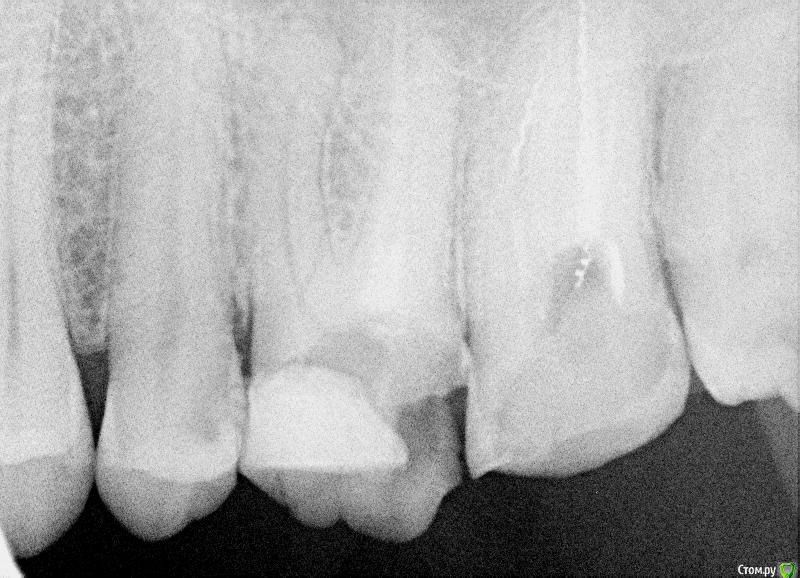

krokomot Опубликовано 24 февраля, 2015 Поделиться Опубликовано 24 февраля, 2015 Пациент решил подлечиться. Выявились проблемы с ранее лечеными по поводу осложненного кариеса зубами.Вот снимки зубов, конкретнее, зуба 2.7 содержащего во всех каналах инородные тела).(2.6 проходит ретритмент), но есть и КТ на нем в области фуркации 2.7 стенка менее 0,5 мм.Имеются признаки одонтогенного синусита (Ренгенологические) клинических нет. Вот вопрос кто-нибудь взлся бы детать ретритмент такого особенного зуба? Ссылка на комментарий

krokomot Опубликовано 25 февраля, 2015 Автор Поделиться Опубликовано 25 февраля, 2015 А вас не смущает выведение материала за верхушку и формирование вокркг него гранулемы? Ссылка на комментарий

DmitrySH Опубликовано 25 февраля, 2015 Поделиться Опубликовано 25 февраля, 2015 Нет, материал не смущает. Гранулему можно только предположить, как-то не четко все в периапексе Ссылка на комментарий

orthophil Опубликовано 25 февраля, 2015 Поделиться Опубликовано 25 февраля, 2015 Каналонаполнители/ lentulo в силере да еще и в верхней половине. Работать можно. Ссылка на комментарий